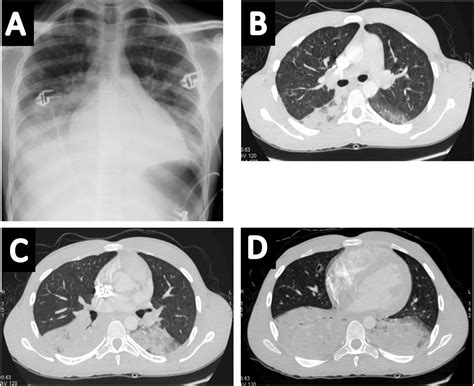

The Role of Diagnostic Imaging